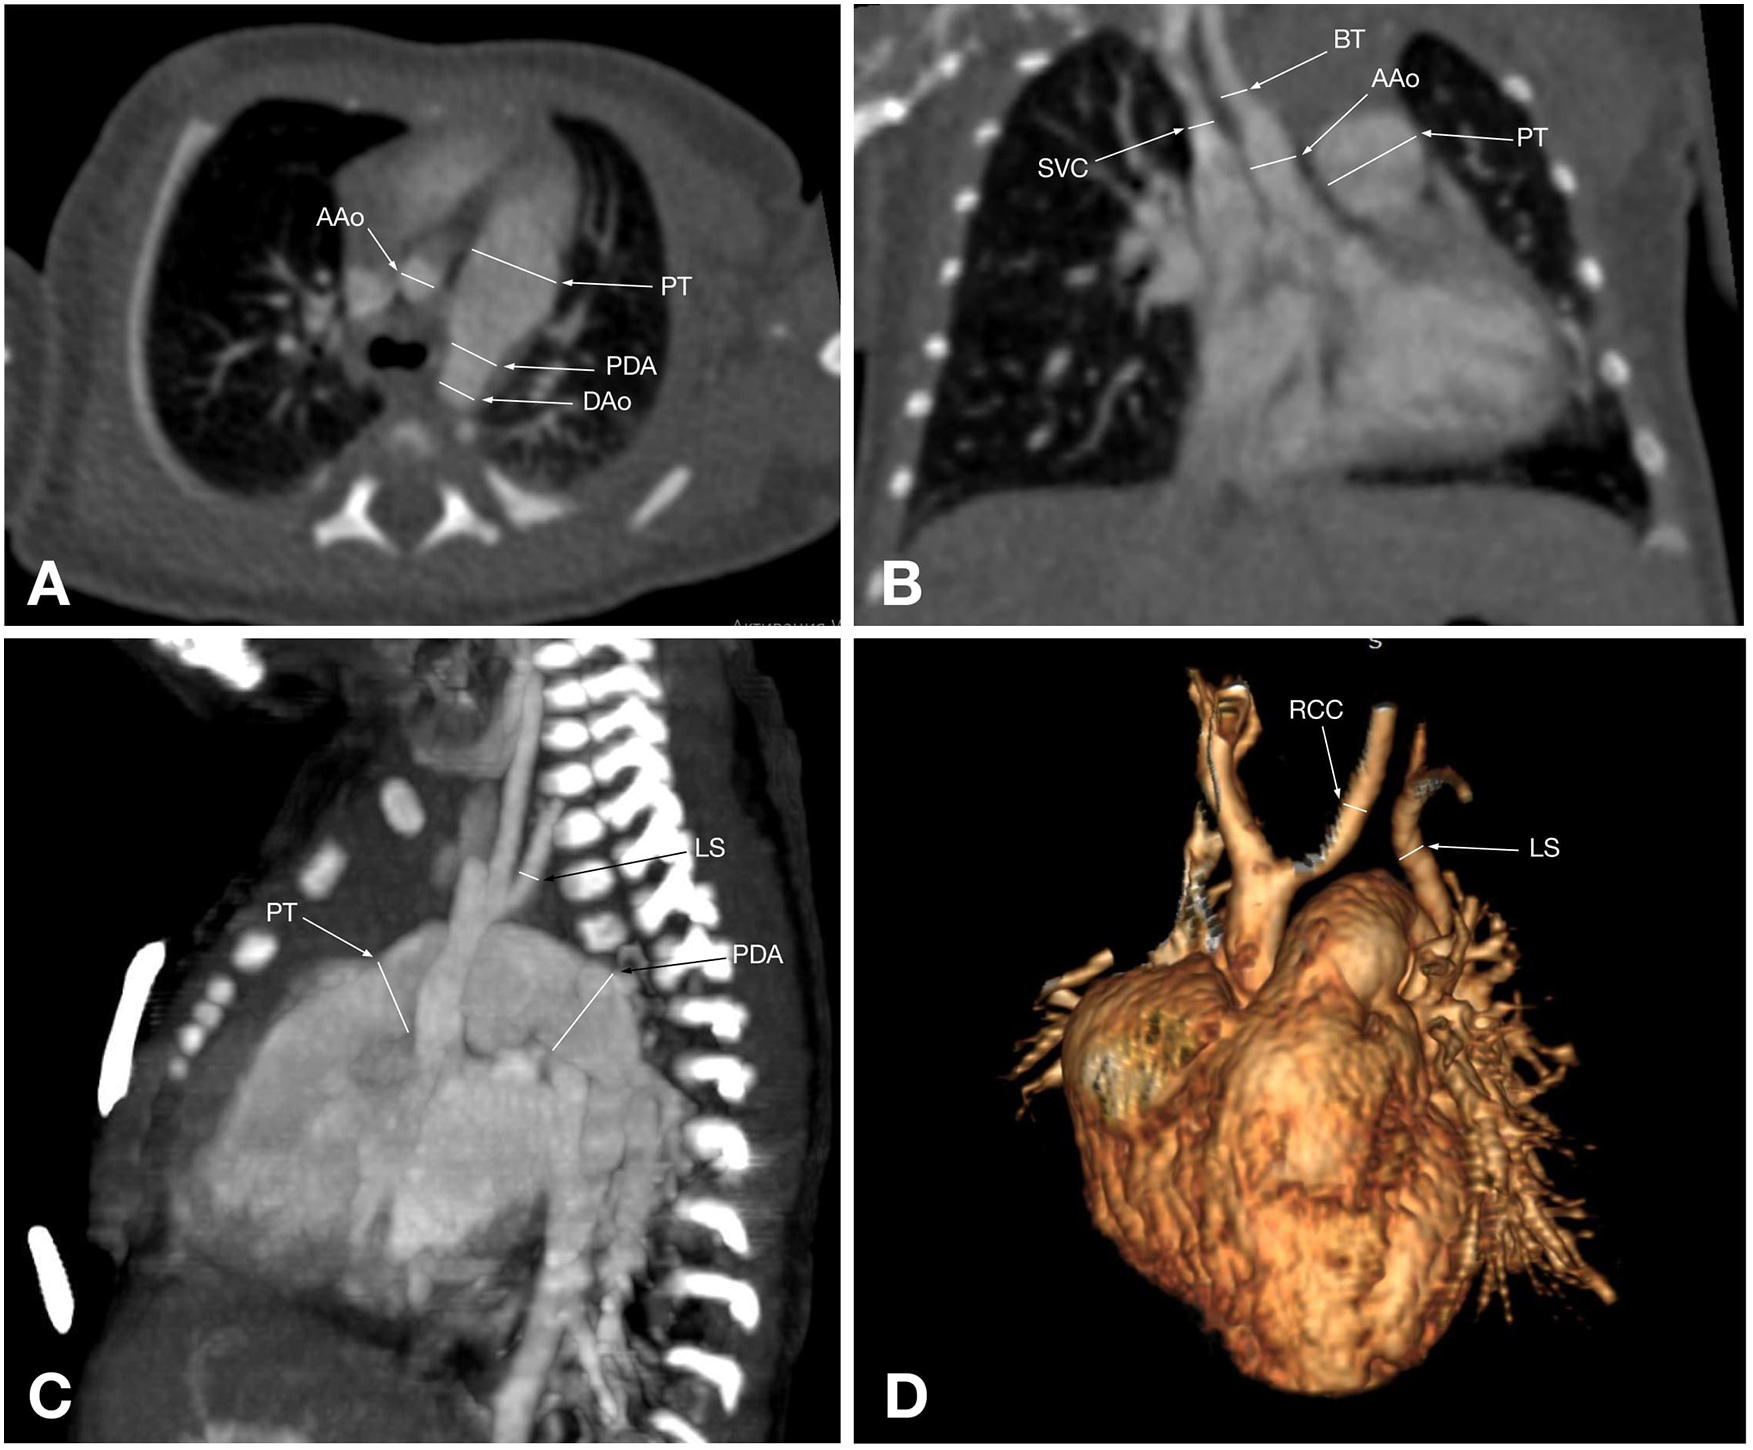

CTA provides a detailed visualization of AA anatomy and its spatial relationships with adjacent organs. Its advantage is further enhanced by various post-processing techniques, such as volume rendering, maximum intensity projection, and multiplanar reformatting, which can be applied to all structures within the scanned volume, making it superior to other imaging modalities for evaluating AA anomalies (5) (Figures 2, 3). Also, CTA is widely utilized for proper treatment and follow-up, as well as for preventing morbidities and mortalities (40). Traditionally, CT scans have been associated with high radiation exposure; however, recent advancements in radiation dose reduction technologies have significantly lowered the levels of exposure (41).

Figure 2. CT angiographic multiplanar images of a 2-day-old patient with type B IAA: (A) axial plane shows the ascending aorta (AAo), followed by the patent ductus arteriosus (PDA), which connects the dilated pulmonary trunk (PT) and the descending aorta (DAo); (B) coronal plane shows the ascending aorta (AAo) and its branch brachiocephalic trunk (BT), next to which are the superior vena cava (SVC) and the enlarged pulmonary trunk (red arrow); (C) Maximum intensity projection of the reformatted sagittal aorta image shows an interrupted aortic arch just distal to the left subclavian artery origin (LS) and the pulmonary trunk (PT), which is connected to the descending aorta via the patent ductus arteriosus (PDA); (D) 3D reconstruction shows an interrupted aortic arch after the right common carotid artery (RCC) arises, and the left subclavian artery (LS) originates from the descending aorta, corresponding to type B IAA.